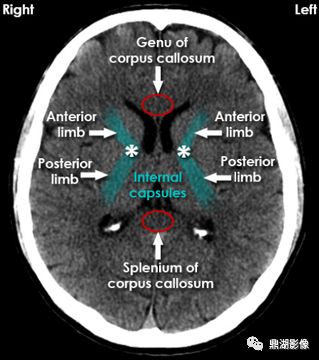

Genu of corpus callosum:胼胝体膝部;Splenium of corpus collosum:胼胝体压部;Internal capsules (posterior anterior limb):内囊(后 前肢) 医学百科网 | YxBaike.Com